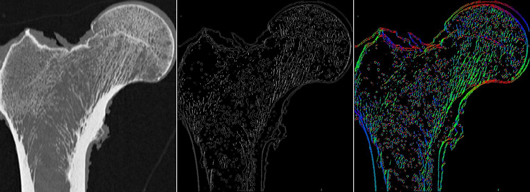

(LEFT) MDCT image of the proximal femur (MIDDLE) same image but pixel values are now

indicative of the magnitude of local structural anisotropy (RIGHT) pixel values are now indicative of

the direction of local structural anisotropy. We investigate the hypothesis that a characterization of

trabecular bone structure that incorporates such bone anisotropy can improve biomechanical

strength prediction in the proximal femur.

Where other researchers have investigated the correlation between bone strength and different features characterizing the trabecular bone, we are specifically interested in using such features (extracted in a non-invasive manner) in conjunction with machine learning techniques for predicting the strength of the femur. Our long term goal is to establish a CADx framework for automated bone strength prediction through non-invasive analysis of the trabecular bone regions of patients with osteoporosis.  We also pursue approaches that characterize the anisotropy of the trabecular bone micro-architecture. The distribution of trabecular bone has been shown to be highly anisotropic (as seen on image shown to the right) and texture features that take this into account could potentially serve as more powerful predictors of bone strength over conventionally used features related to bone mineral density (BMD).